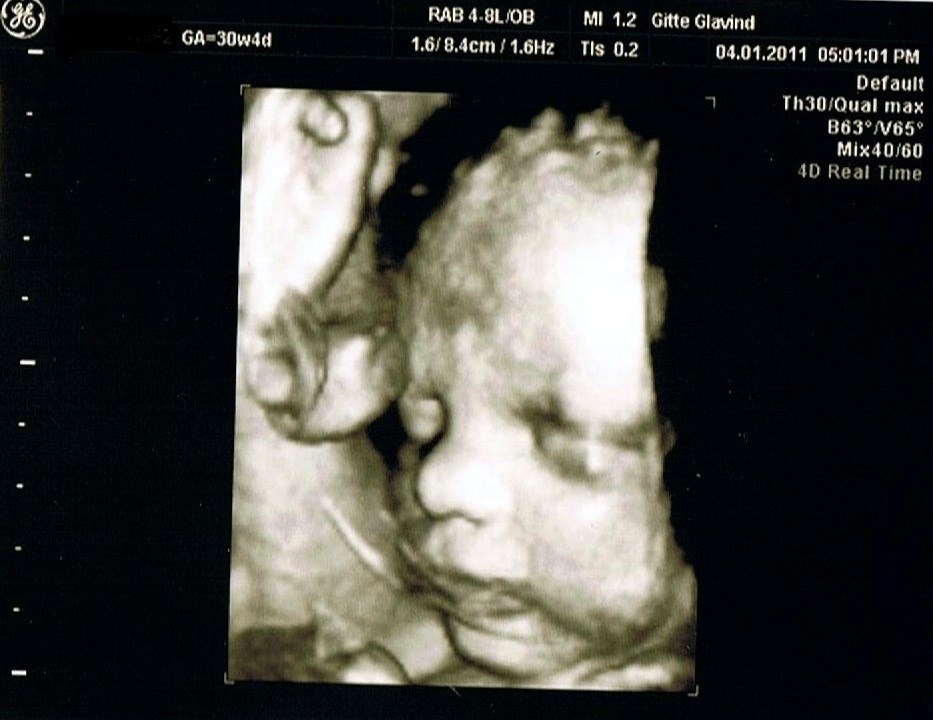

Jeg kan da lige vise Silas frem. 3D billede er fra omkring uge 30 så vidt jeg lige husker.

Vedhæftede fotos (klik for at se i fuld størrelse)

næsen og kinderne ligner da rimeligt..synes i også det?

Jeps synes dog ikke billedet er den bedste kvalitet i 3D, vi har en dvd film hvor det ligner ham meget bedre.